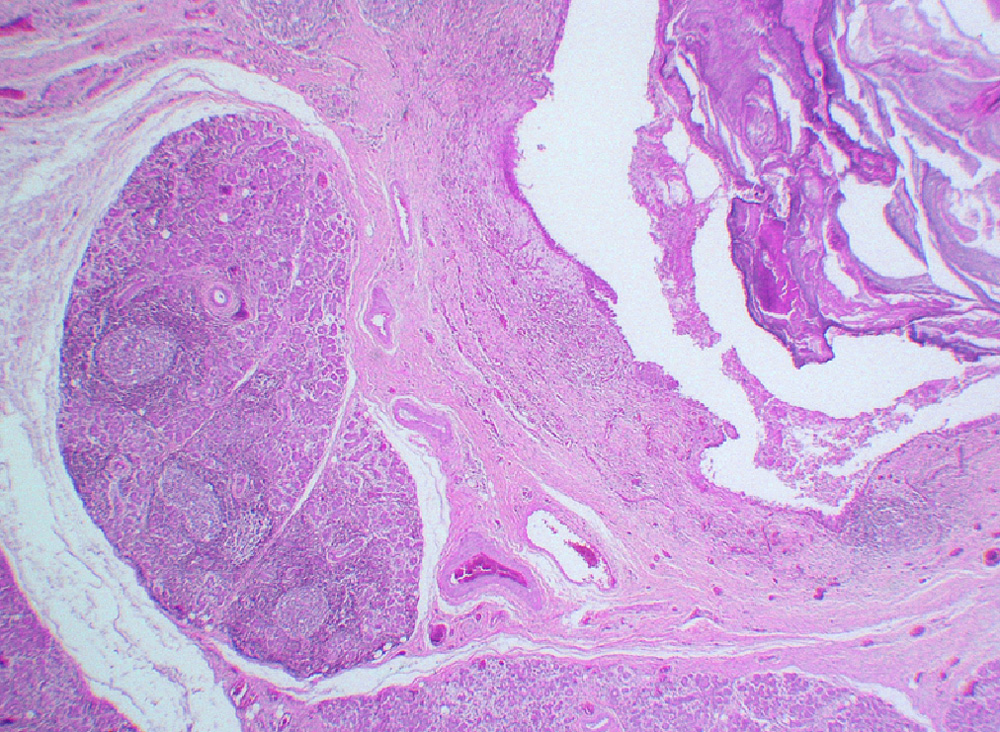

Microscopic finding (HE stain, low-power view). A sialolith (), with concentric laminations, is seen lodged inside a markedly dilated duct. There is pronounced chronic interstitial inflammation of salivary gland lobules () with lymphoid follicle formation (arrows). Intra and perilobular fibrosis are characteristic findings in chronic sclerosing sialadenitis. There is acinar atrophy and destruction with ductal dilatation (lower right).